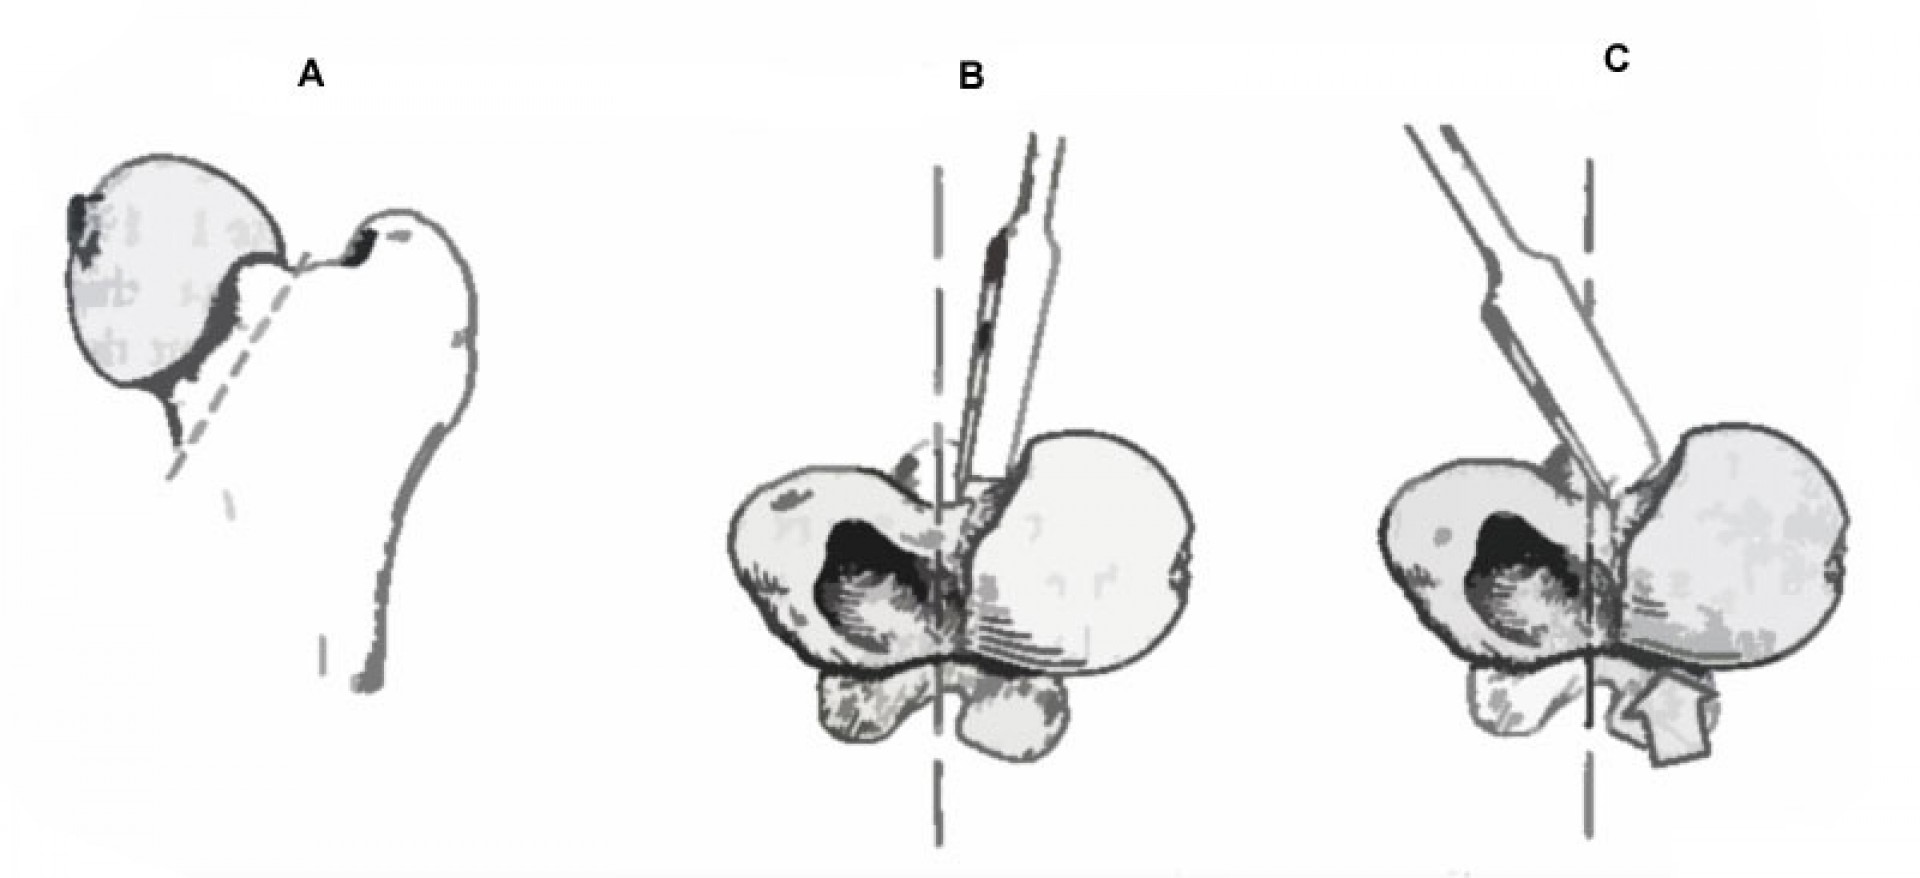

A röntgen felvétellel egyértelműen diagnosztizált betegség műtéti ellátást igényel. A beavatkozás során az elhalt combcsontfejet eltávolítjuk, megszűntetve az ízületi fájdalmat. A gyógyulási folyamat során a csípőízület helyén egy laza kötőszövetes kapcsolat alakul ki (álízület, pseudoarticulatio), mely fájdalommentes mozgást biztosít a medencecsont és a combcsont között.

A műtétet követő időszakban - a varratszedés idejéig - az állat szigorú mozgáskorlátozását írjuk elő. Ezt követően a fokozatosság elvét betartva folyamatosan, először csak pórázon, majd szabadon jártatjuk, majd futtatjuk a beteget a műtétet követő 4 héten át.A betegek szinte minden esetben tünetmentesen gyógyulnak.